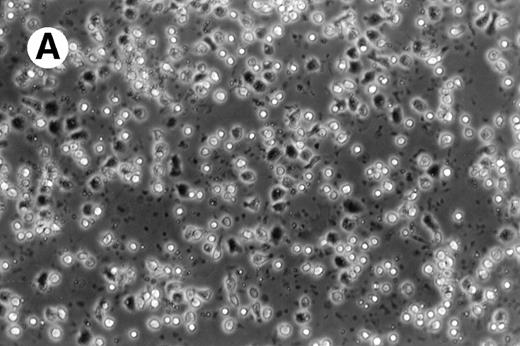

Cultures of AML cells were replenished with fresh medium and cytokines every 3 to 4 days. Cells cultured in various cytokine combinations were assessed for total number of viable cells and cells with dendritic morphology after various culture periods. Approximately 25% to 45% of the initial cell population was recovered after 9 days of culture. No significant change in numbers of cells was observed between day 9 and day 20 of culture (not shown). Similar yields of viable cells were noted for AML cell cultures from other patients. Freshly isolated AML PBMNC displayed a spherical morphology without discernable cells exhibiting dendritic processes (Fig 1A). Between days 10 and 14, cultures with GM-CSF, IL-4, and TNF-α (Fig1B) or GM-CSF, IL-4, and CD40L (Fig 1C) consistently displayed an increase in cell size and showed cell clusters with dendritic morphology in all but one AML patient (patient 16).

Morphology of freshly isolated and cultured AML cells. Phase contrast micrographs of freshly isolated AML PBMNC (A; 100× origonal magnification); AML cells cultured for 14 days in GM-CSF, IL-4, and TNF (B; 250× original magnification); or GM-CSF, IL-4, and CD40L (C; 250× origianl magnification). (A and B) Obtained with cells from patient 13; (C) Obtained with cells from patient 18.